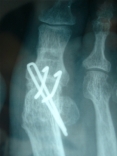

Par des vis croisées ou axiale unique:

Radiographies de ce cas:

C'est le montage de référence de l'auteur et le plus pratiqué actuellement chez les chirurgiens du pied.